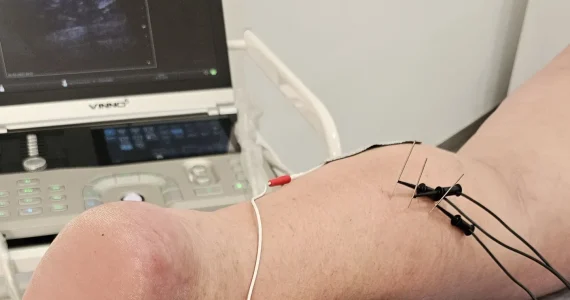

Valoración ecográfica

Leer más sobre valoración ecográfica

La ecografía es una prueba de diagnóstico por imagen que utiliza ondas sonoras para crear imágenes de órganos, tejidos y estructuras del interior del cuerpo. Permite a su profesional de la salud observar al interior del cuerpo sin una cirugía.

En Zona Salud Llerena disponemos de un ecógrafo para complementar nuestras valoraciones clínicas, mejorar el seguimiento de nuestro paciente y realizar ciertos tratamientos como son la neuromodulación o la EPTE.